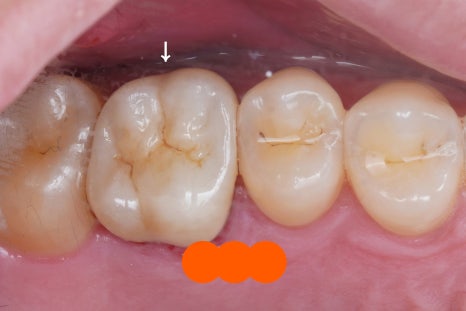

지르코니아 크라운 (큰어금니)

처음 사진과 비교하면 어떤가요

너무나도 자연치아와 비슷하게

잘 마무리 된 것 같습니다.

다시한 번 비교해볼까요?

전 후

저희가 믿고 협업하고 있는

치과 기공소 소장님께서

실력이 워낙 좋으시니까

제가 뭐 따로 조정할 것도 없었어요

원칙대로

너무 빡빡하거나 헐겁게 끼워지지 않는지,

형태적으로 이상이 없는지,

치아와 크라운의 경계가 턱지지 않았는지,

씹을 때 교합은 어떤지,

그리고 색상까지 제가 체크했는데

다 알맞게 잘 해주셨습니다. 역시!

만약 다른 치과 선생님께서 보신다면

엑스레이 찍어보지 않는 한

크라운 치료를 했는지도 헷갈리실 거예요

저도 기록을 보지 않으면 헷갈릴걸요?